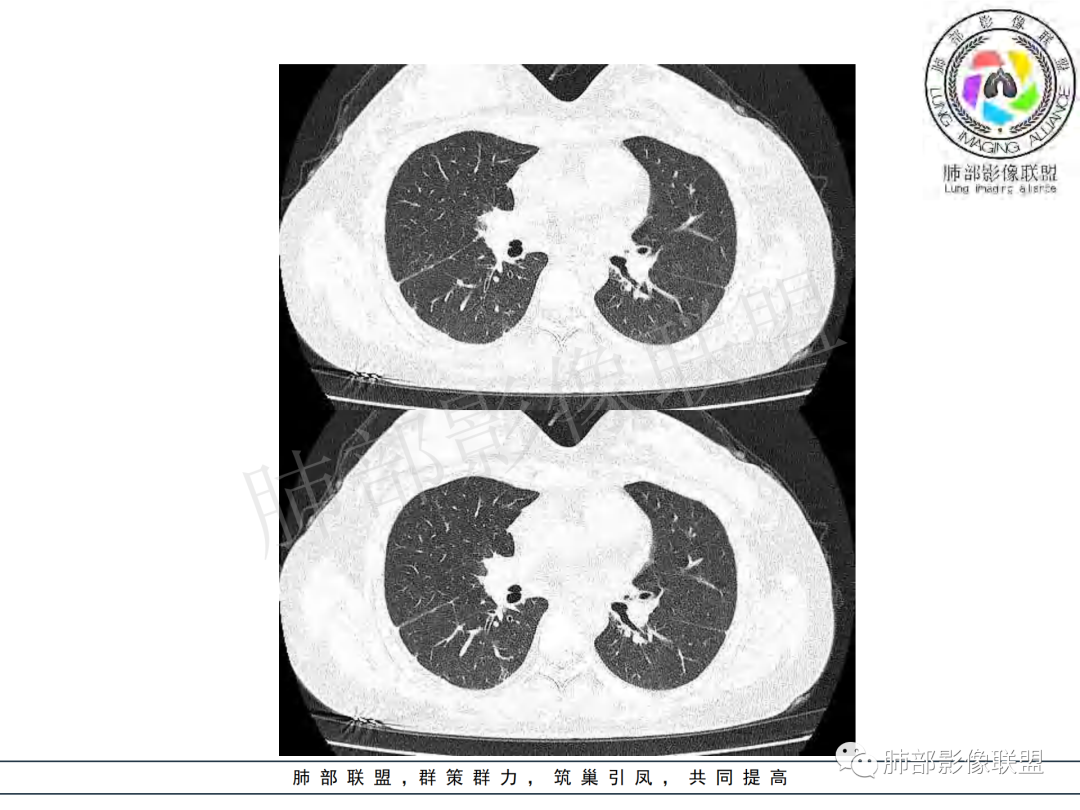

右肺肺门旁肿块,右肺中间段支气管腔内结节,增强强化不均;纵隔多发淋巴结环形强化,右侧少量胸腔积液,临床发热入院,考虑结核,鉴别肿瘤。

右肺门增大,远端花花草草不明显,支气管管壁增厚,纵隔淋巴结环形强化,年龄,病程,考虑炎性病变,结核可能,有个层面支气管截断,有强化,鉴别粘表。

女,20,病程长达8月,发热、胸痛、右侧胸腔积液病史。胸部CT:右肺门旁不规则肿块影,右中间支气管腔内结节,纵隔多发淋巴结肿大;强化不均匀,灶性坏死灶,环形强化;右侧少量胸腔积液并局部肉芽肿样突起。年轻女性,长病程,多部位,考虑慢性炎症,结核?鉴别肿瘤。

青年,右肺门增大,见软组织肿块影,部分支气管腔结节,并管腔狭窄,增强后明显不均匀强化,伴纵隔多发肿大淋巴结,环形强化,考虑恶性,类癌,鉴别支气管内膜结核

右肺门不规则肿块,向气管腔内生长,不均匀强化,其内粘液栓,纵隔淋巴结增大,部分有坏死,胸膜结节强化,考虑恶性,粘表?类癌?鉴别结核

右肺肺门旁肿块,右肺中间段支气管腔内结节,增强强化不均;纵隔多发淋巴结环形强化,右侧少量胸腔积液,考虑结核可能,鉴别肿瘤。

年轻女性,慢性病程,发热、胸痛。右肺门旁不规则肿块影,纵隔多发淋巴结肿大;强化不均匀,环形强化;右侧少量胸腔积液;首先考虑结核,鉴别肿瘤,结节病。

女性,20岁。高热、畏寒。右肺上叶近肺门区不规则肿块,周围斑点、片小结节影伴肿大淋巴结,肿块包绕并突入右主支气管腔内,增强后肿块不均匀强化,淋巴结环形强化中心低密度,考虑结核。

本例患者,年轻女性,慢性病程,多次抗感染治疗效果不佳,实验室检查示白细胞及中性粒细胞不高,不支持普通细菌感染,虽然肺泡灌洗液X-Pert检测阴性,结合患者胸部CT结核感染亦不能排除,胸部CT主要表现为右侧肺门及纵隔淋巴结肿大,仔细观察不难发现右中间支气管内新生物凸向管腔内,增强扫描,右肺门(10R)及纵隔淋巴结(2R,4R)明显不均匀强化,内部呈不规则低密度无强化区,被周边高强化区包绕(环形强化)的特点,首先应当想到纵隔淋巴结结核诊断。淋巴结分布亦不符合肺部恶性肿瘤迁徙途径。